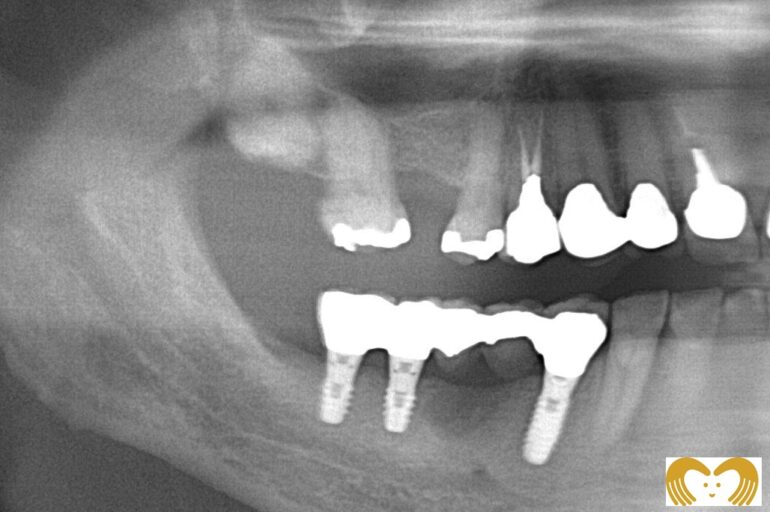

症例写真-1-

こちらは実際にインプラント治療を受けた方のビフォーアフター画像になります。